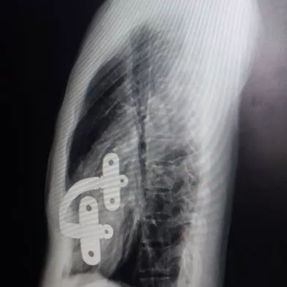

Incisions were made along the previous surgical scars on both sides of the chest wall to remove the bars placed during the Nuss procedure. Then, the cyst on the left anterior chest wall was explored and incised through the incision on the left side of the chest wall, and the contents of the abscess were thoroughly debrided. A third incision along the midline scar allowed careful pre-shaping of the depressed bony structure of the anterior chest wall. Two bars were then implanted to complete the Wung procedure. Postoperatively, the chest wall appearance was restored to normal.

4. Failure to Embed the Bar Within Muscle Tissue: In corrective surgeries, bars are typically embedded within the chest wall muscles to facilitate proper healing of the incision and minimize the risk of complications. However, in this patient’s initial surgery, the bar was positioned directly beneath the skin without any muscle coverage. This lack of protective tissue caused constant friction between the bar and surrounding tissues, eventually leading to the development of the abscess.